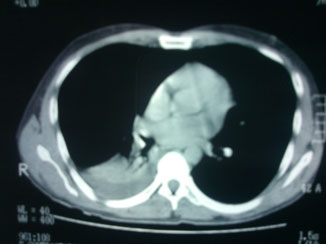

La tele de tórax mostró un hemidiafragma derecho elevado con nivel hidroaéreo, por lo que hubo sospecha de absceso pulmonar (figuras 3 y 4). Por lo tanto, se llevó a cabo una TAC de tórax en la que se observó una imagen redondeada con doble nivel hidroaéreo de aspecto tabicado, condensación basal derecha y derrame pleural, sin adenomegalias. El reporte de radiología fue de empiema derecho (figuras 5 y 6).

Se administró un doble esquema antibiótico con carbapenémico y fluoroquinolona. Los exámenes de laboratorio de ingreso al servicio de Urgencias reportaron los siguientes valores: glucosa 117, BUN 20, urea 43, creatinina 1.2, ácido úrico 3, colesterol 149, triglicéridos 87, bilirrubina total 1.1, bilirrubina directa 0.3, bilirrubina indirecta 0.8, AST 25, ALT 40, amilasa 211, lipasa 1820. Leucocitos 10 500, Hb 12.4, Hto 36, plaquetas 261 00. El examen general de orina (EGO) presentó proteinuria de 100 mg/dL. El paciente ingresó a Medicina Interna, se mantuvo estable sin vómica, sin fiebre ni manifestaciones de respuesta inflamatoria sistémica, sin datos de sepsis, no se integró síndrome pleuropulmonar. Después de10 días de tratamiento antibiótico se le tomó una nueva TAC de tórax (figura 7) en la que se visualizaron las haustras del colon derecho interpuestas entre el hígado y el diafragma. Se diagnosticó síndrome de Chilaiditi al observar signo de Chilaiditi, además de sintomatología abdominal, pancreatitis aguda leve por elevación de lipasa y reporte tomográfico, así como neumonía basal derecha. Se completó el tratamiento antibiótico y el paciente egresó de manera estable.